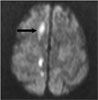

MRI scans of the head revealed acute infarcts (arrows) in the right corona radiata, right centrum semiovale, and anterior and posterior corpus callosum.

In this patient, the syndrome manifested by her left hand can be attributed to the posterior callosal infarct, while the grasping nature of her dominant right “alien” hand may result from a new anterior callosal infarct combined with the prior parietal lobe infarct. Despite the association of this syndrome with Alzheimer- type dementia, we believe our patient's condition was related to the new infarcts.